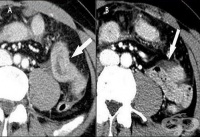

S36.4 Травма на тънко черво

От закритите наранявания на храносмилателния тракт най-голям процент се пада на нараняванията на тън...